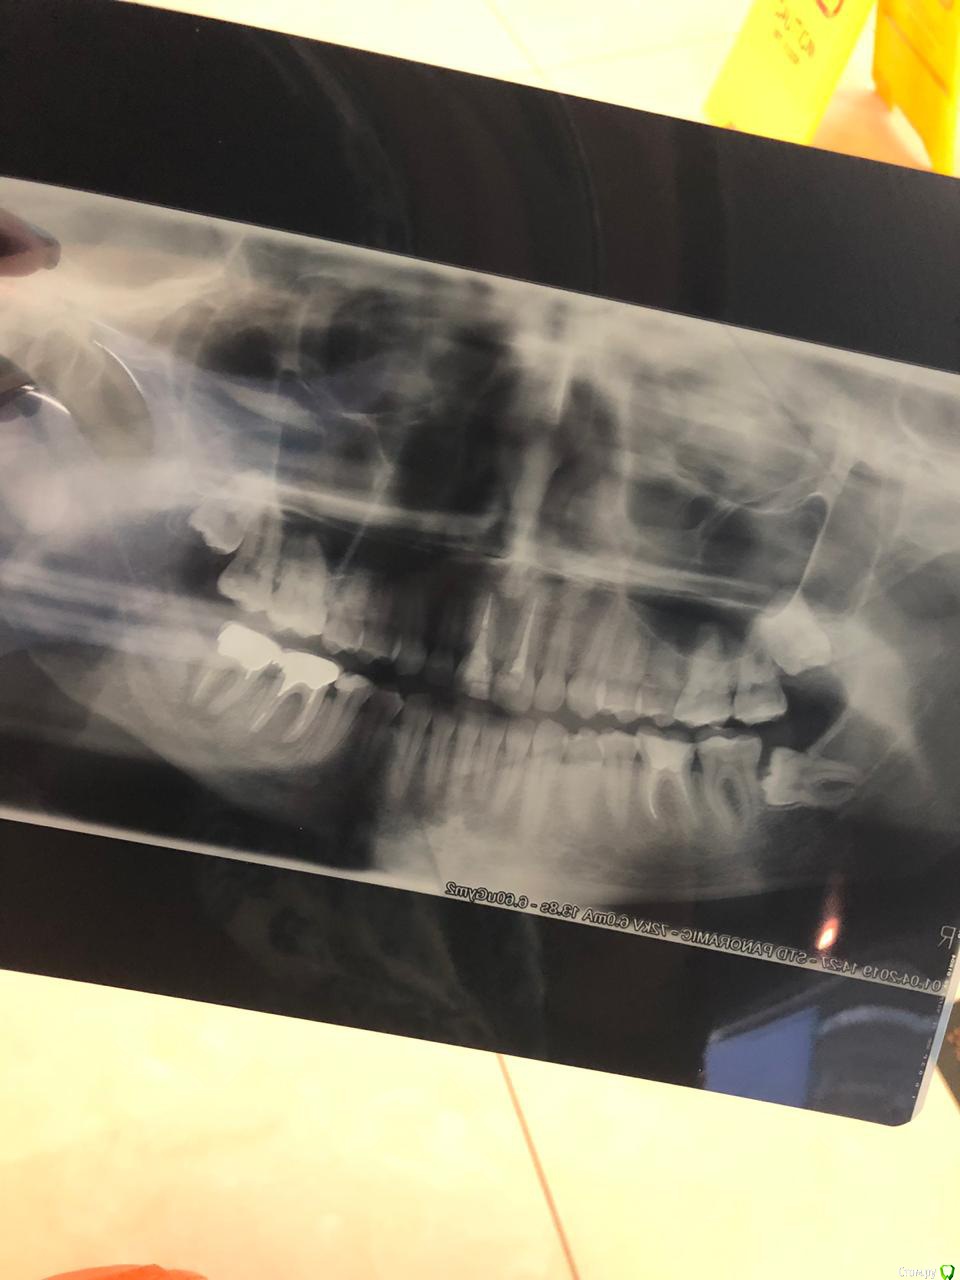

newbornmsk Опубликовано 29 декабря, 2019 Поделиться Опубликовано 29 декабря, 2019 Добрый день!С детства проблемные зубы, очень низкие и кушаю можно сказать десной. Поставили мне хронический пародонтинт. Речь идёт о 36 и 37 зубе, стоят металические колпачки и коронки, год назад было воспаление, сделала рентген. Стоматолог сказал, что это из-за того, что пища забивается в карманы зубы, прочистила , все исчезло ровно на год. Сейчас поменяли коронки (были как мост 2 зуба), на одинарные. Десна была перед заменой коронок очень воспалённая, пролечила (как казалось). Прошла неделя, образовался свищ гнойный, сделала прицельный снимок-стомотолог снова говорит , что это из-за того что еда попала в карманы, воспаление идёт от верхушек корней(она уехала до 7 января, сказала пить цифран СТ и полоскать. Врач в клинике, где я делала снимок, сказала что у меня 2 кисты по 36 и 37, нужно снимать все конструкции и прочищать каналы , но гарантии что не сломает корешок зуба не даёт. Я пью таблетки, полоскаю и плачу. Что делать? Буду благодарна за советы. (Прикрепляю снимок от апреля 2019 года и двухдневный) Ссылка на комментарий